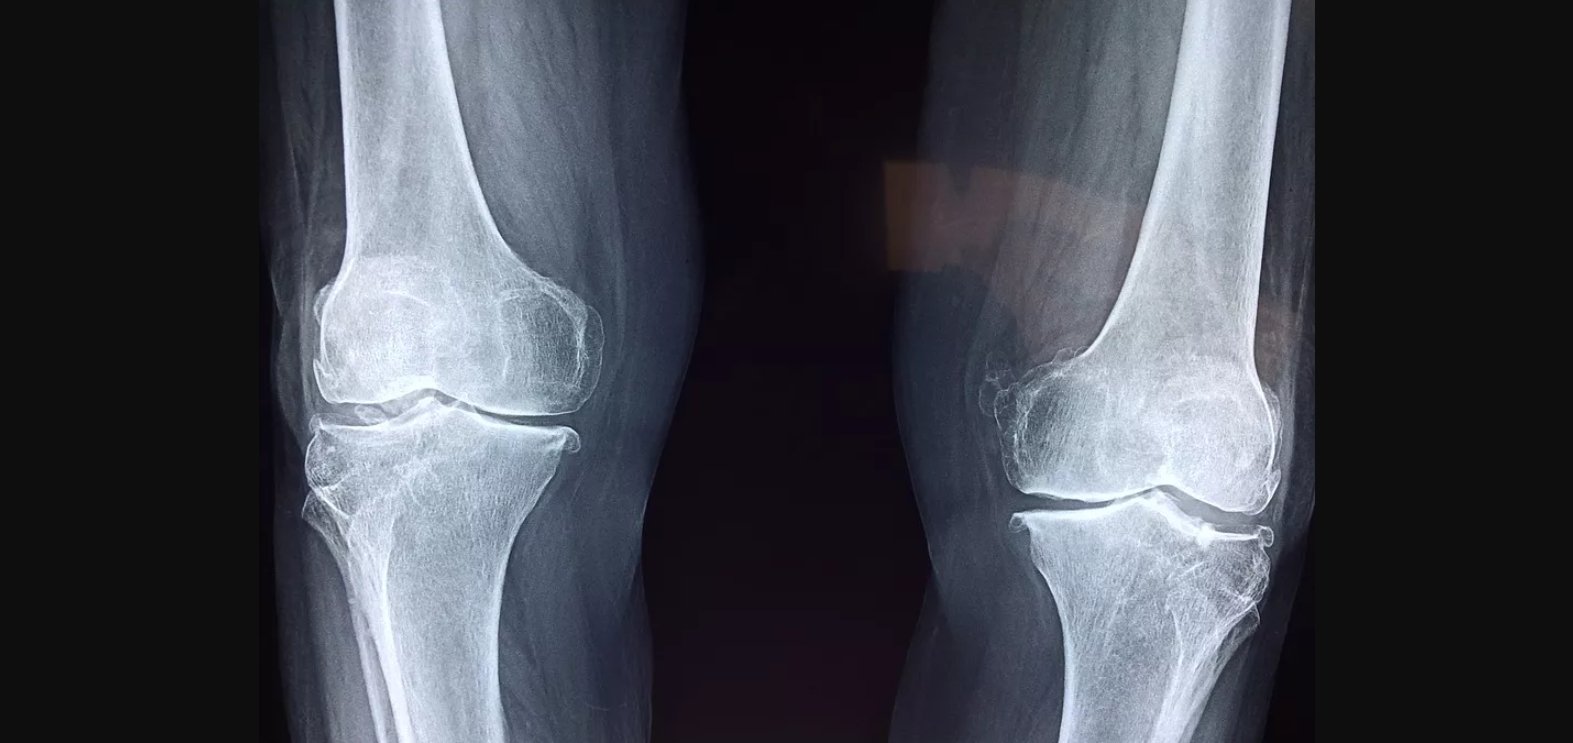

Тендинопатия коленного сустава: симптомы и лечение